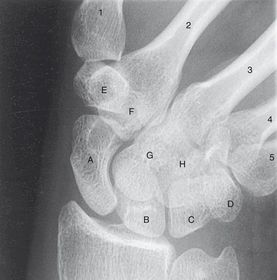

Ulnar Deviation